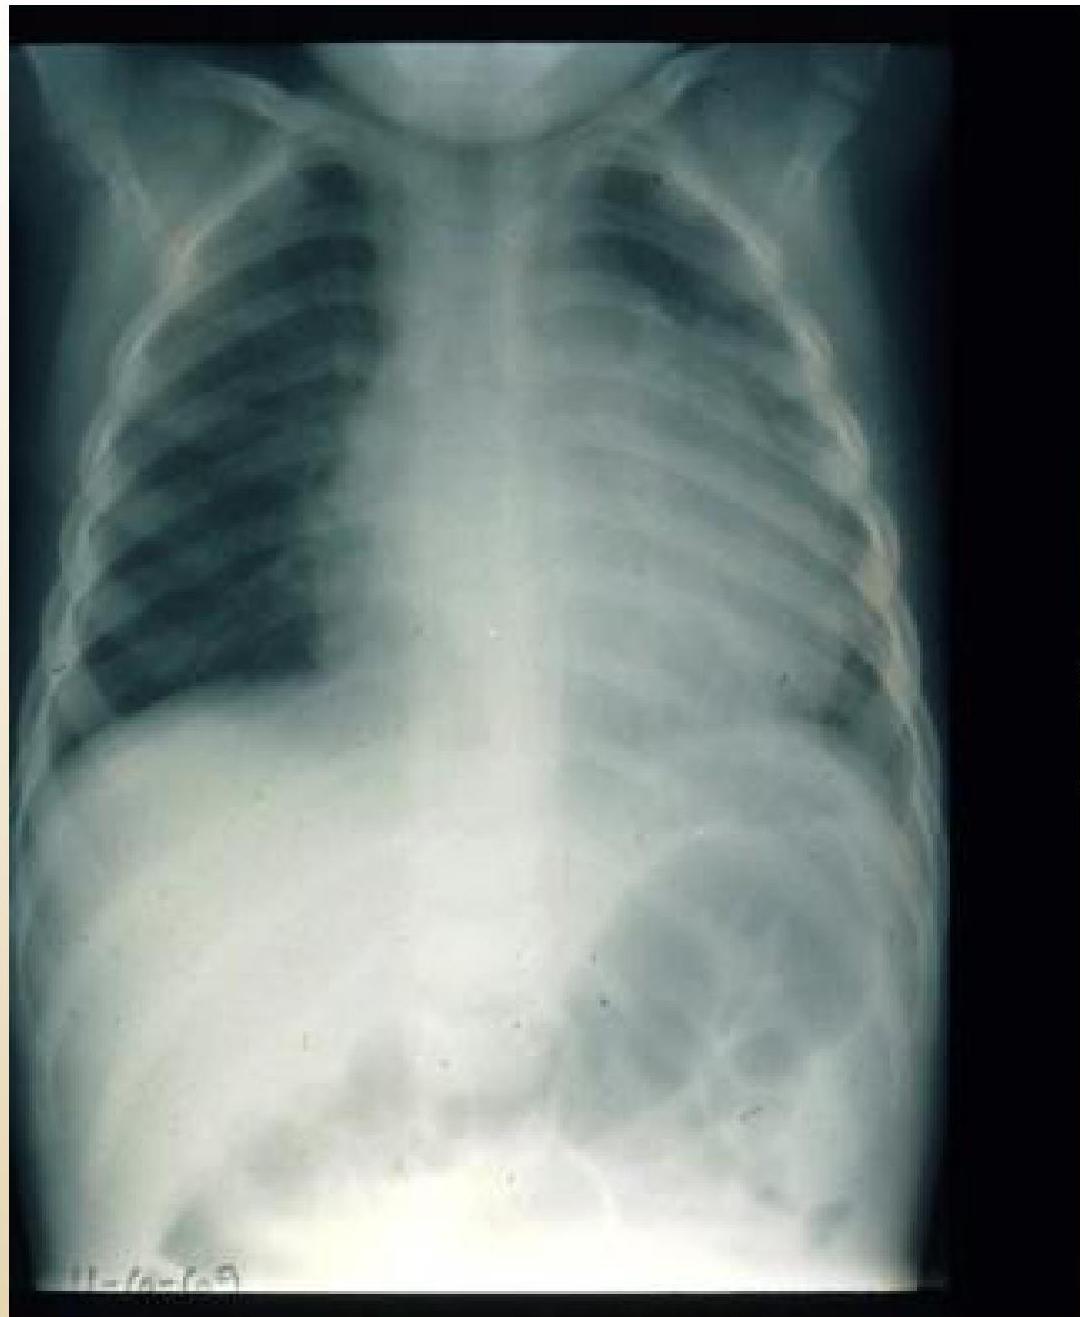

- Serositis:

- Pleural and pericardial effusions.

- Chest pain/shortness of breath (signs of pericarditis/pleuritis).

- Friction rub may occur.

Pericardial Effusion:

X-RAY of child with pericardial effusion